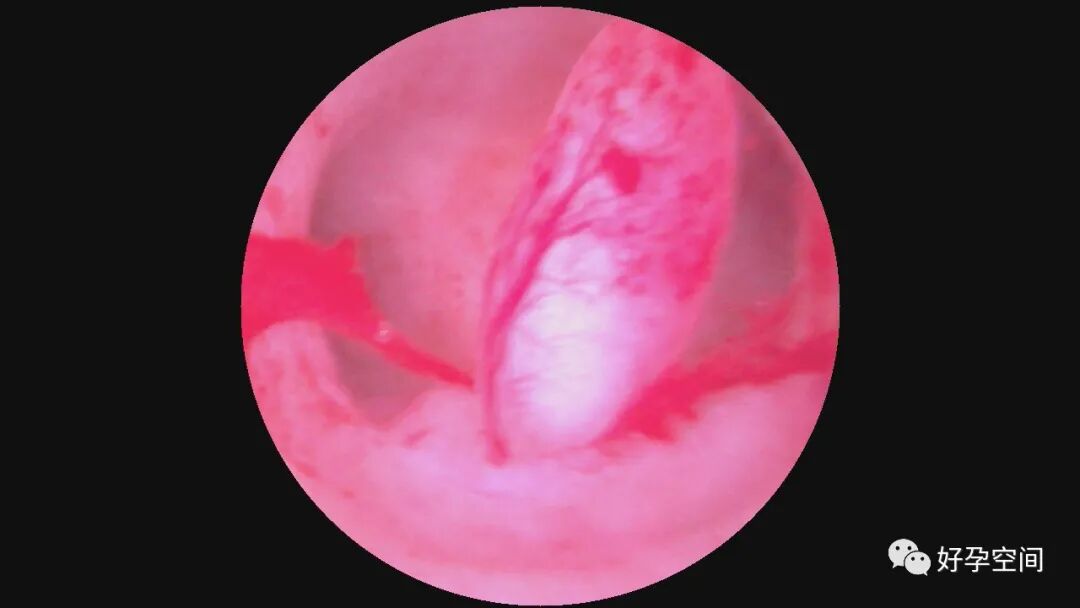

病例2:51岁,G2P1,顺产1次。安环29年,绝经1年,发现宫颈息肉1月。一次性宫腔镜见T型环嵌顿于宫腔,铜环套破碎,异物钳取出。宫颈管息肉约2.5cm*1.5cm*1.0cm,息肉根部位于宫颈管下段前壁,单级电针切除息肉。